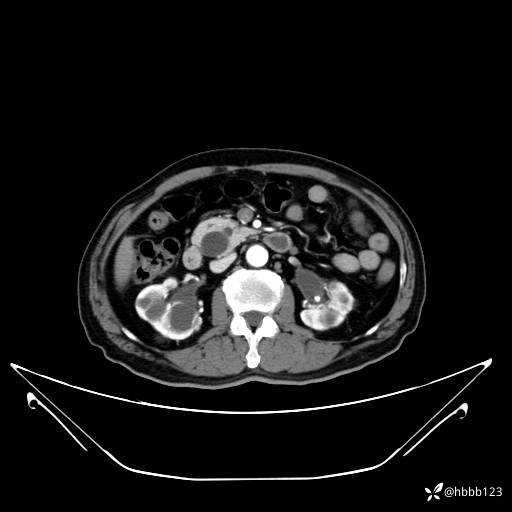

延迟期: